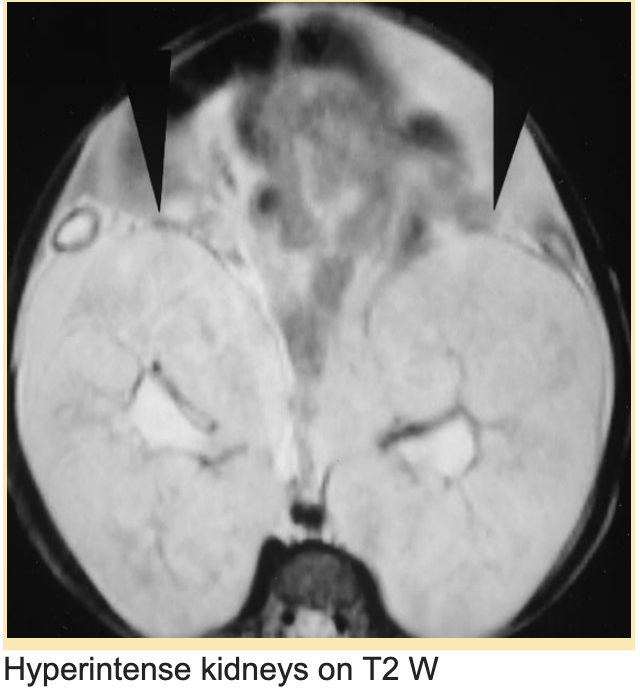

12/ In cases with ambiguous findings on ultrasound, MRI confirms the diagnosis.

🔶Hyperintense enlarged kidneys on T2W

🔶RARE-MRI (rapid acquisition with relaxation enhancement)- microcystic dilatation & hyperintense, linear radial pattern in the cortex & medulla.

PMID 10755752